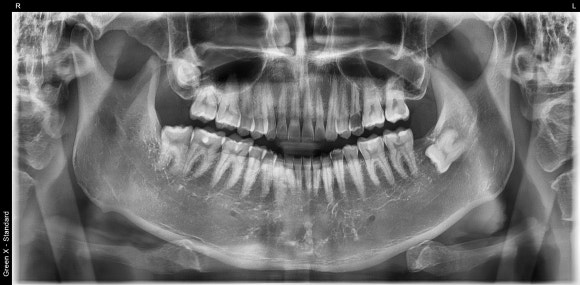

치과 진단의 기본 중의 기본,

파노라마 엑스레이입니다.

아직도 치과에서

"엑스레이는 안 찍을래요" 하시는 분이 계신지요?

눈에 보이지 않는 영역까지

확인해야,

비로소 정확한 진단과

환자분께 딱 알맞는 치료를 전해드릴 수 있습니다.